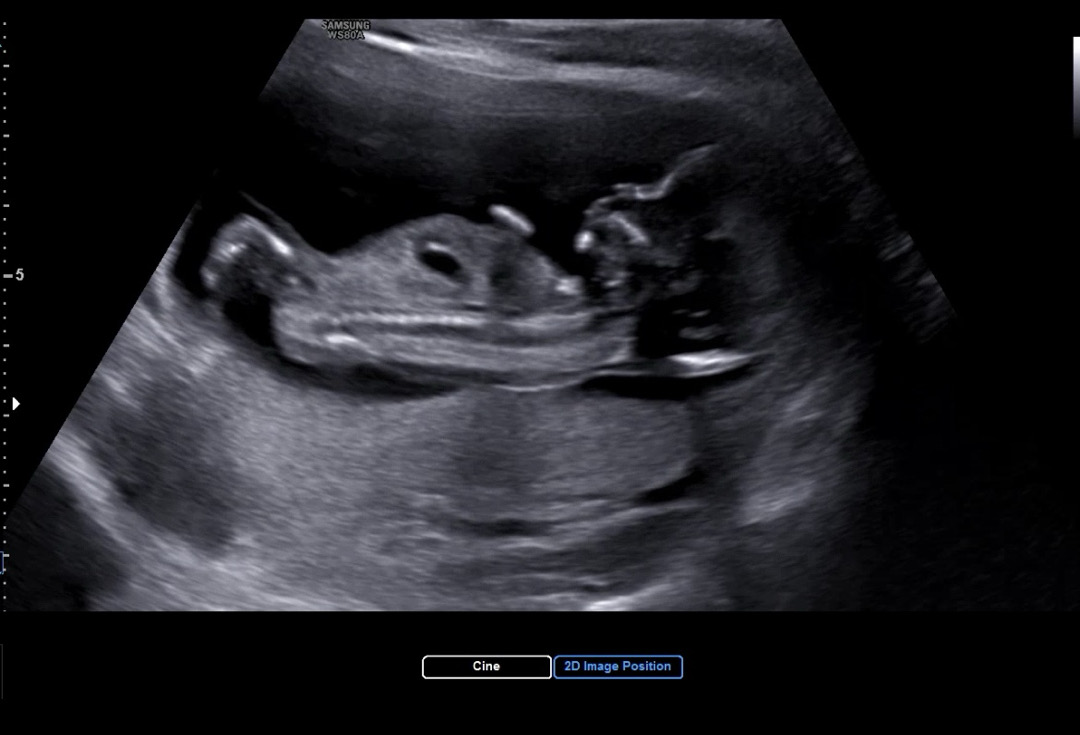

12주 3일 각도법 참견 부탁드립니다 🤍

아들일까요 딸일까요 ?